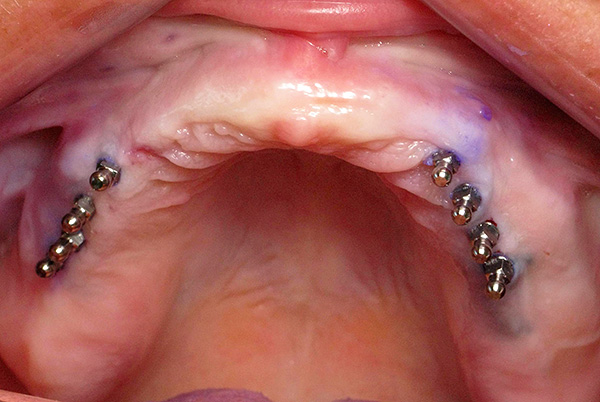

Procedimento de implantação padrão

Para instalar mini-implantes, basta fazer um orifício na membrana mucosa até o osso nos locais selecionados. O sangramento leve que começa após uma punção não interfere com outras manipulações.

Através dos orifícios preparados, um orifício é então perfurado no osso no qual o implante é parafusado.Nesse caso, o orifício é feito com um diâmetro menor que o diâmetro da rosca do implante, e a própria rosca durante a instalação não apenas fixa rigidamente o implante, mas também aperta o próprio osso. Graças a isso, o mini-implante pode ser carregado imediatamente com uma prótese.

O procedimento para instalar um mini-implante leva de 5 a 10 minutos e é realizado sob anestesia local. Ao mesmo tempo, o paciente não sente dor ou sensações desagradáveis; portanto, na maioria das vezes, as pessoas respondem bem à instalação desses implantes.

No caso comum, a prótese é instalada alguns dias após o implante. As impressões são feitas imediatamente após a fixação dos implantes e a técnica é dada ao laboratório.

Às vezes, de acordo com o médico, é possível causar uma impressão antes da instalação dos implantes, para que a prótese esteja pronta para o procedimento e o médico a instale imediatamente após o implante. No entanto, nesse caso, a posição dos implantes deverá ser “customizada” para encaixar os ninhos na prótese e, em casos raros, são possíveis inconsistências.